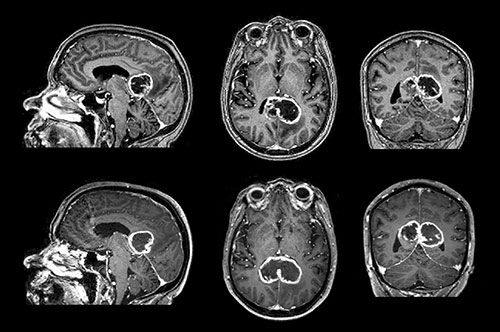

Figuren viser kontrastforsterkede T₁-vektede MR-bilder av et sommerfugl-gliom med kraftig perifer kontrastoppladning og sentral nekrose, typisk for et glioblastom. Sommerfugl-gliomer infiltrerer oftere fremre del av corpus callosum (≈ 60  %), mens midtre del (≈ 30  %) og bakre del (≈ 10  %) er sjeldnere (1). Symptomatisk kan slike svulster ofte resultere i såkalte frakoblingssyndromer som aleksi, agrafi og apraksi, i stedet for ordinære sensomotoriske utfall. Ensidig apraksi kan for eksempel ses dersom språkområdene på venstre side ikke lenger er forbundet med de motoriske områdene i høyre hjernehalvdel. Pasienten klarer da ikke å utføre kommandoer med venstre hånd, men klarer det godt med høyre hånd.

Et sommerfugl-gliom er et gliom som involverer begge hjernehalvdelene ved at det vokser gjennom corpus callosum, nervebanene som krysser midtlinjen i storhjernen. Når svulsten vokser symmetrisk i de to hjernehalvdelene, får man et karakteristisk bilde som minner om en sommerfugl. Differensialdiagnoser ved sommerfugllesjoner i corpus callosum er lymfom i sentralnervesystemet, tumefaktiv multippel sklerose og toksoplasmose.